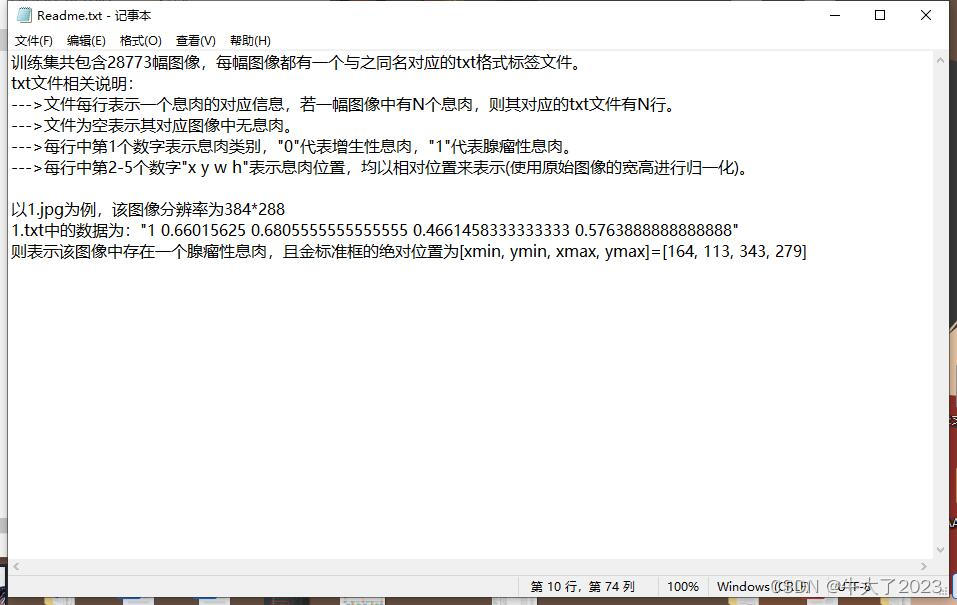

但有一些比赛和开源项目会提供图片+标注数据集供参赛选手,比如这个小比赛提供了现成的数据集,附上说明图片

训练集:28773 幅结直肠息肉内镜图像(原始图像、标签和 Readme 文件)。网盘链接如下:链接: https://pan.baidu.com/s/1n08y04DokW5LyF0t7tMIog提取码: tmkn